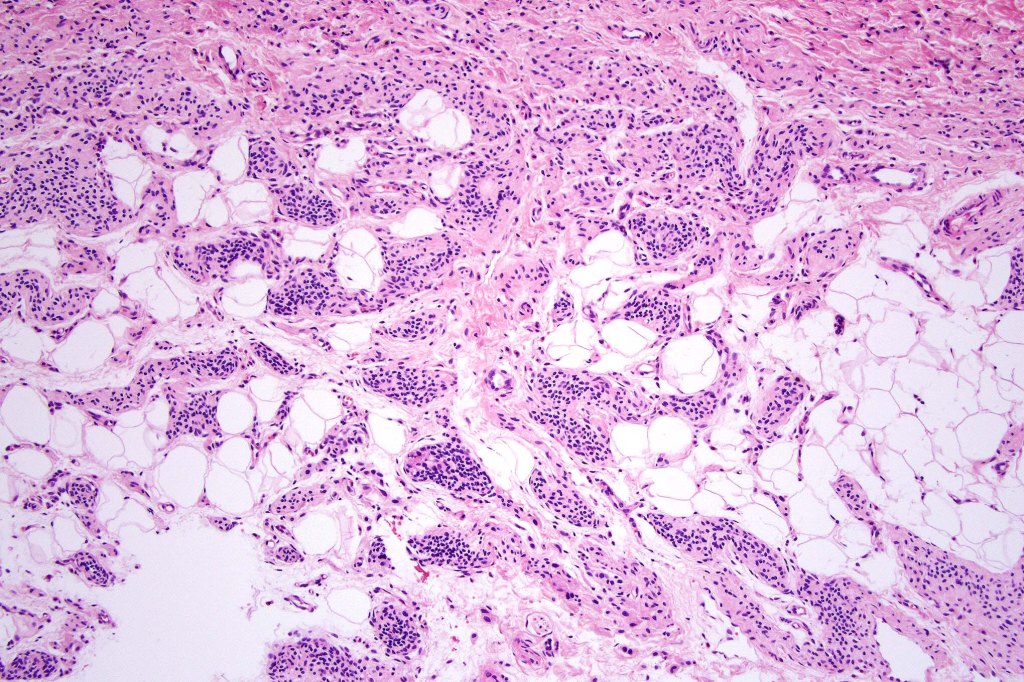

Histological features

•The nodule generally merges with the adjacent nevus but sometimes it can be sharply circumscribed

•It is hypercellular and most often composed of epithelioid cells showing little pleomorphism & only occasional mitoses

•Nuleoli are small

•Intracytoplasmic pseudo-inclusions

•The constituent cells are generally larger than the adjacent nevus cells

•Some examples show more marked pleomorphism with prominent nucleoli and increased mitotic activity but abnormal mitoses are not a feature. These are not associated with any sinister biological potential

•Absence of necrosis, hemorrhage or Pagetoid spread in the overlying epidermis

•Spindle cell, small blue cell, blue nevus-like features, Spitzoid & proliferative nodules with mesenchymal differentiation (myofibroblastic, chondroid & osteoid) can be seen